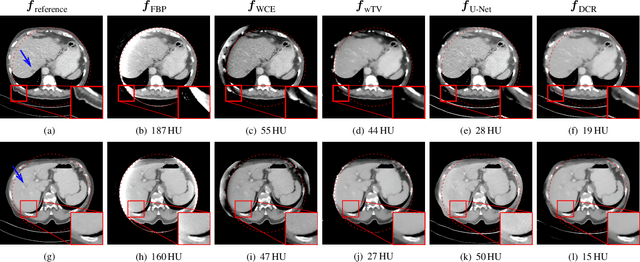

Image reconstruction from insufficient data is common in computed tomography (CT), e.g., image reconstruction from truncated data, limited-angle data and sparse-view data. Deep learning has achieved impressive results in this field. However, the robustness of deep learning methods is still a concern for clinical applications due to the following two challenges: a) With limited access to sufficient training data, a learned deep learning model may not generalize well to unseen data; b) Deep learning models are sensitive to noise. Therefore, the quality of images processed by neural networks only may be inadequate. In this work, we investigate the robustness of deep learning in CT image reconstruction by showing false negative and false positive lesion cases. Since learning-based images with incorrect structures are likely not consistent with measured projection data, we propose a data consistent reconstruction (DCR) method to improve their image quality, which combines the advantages of compressed sensing and deep learning: First, a prior image is generated by deep learning. Afterwards, unmeasured projection data are inpainted by forward projection of the prior image. Finally, iterative reconstruction with reweighted total variation regularization is applied, integrating data consistency for measured data and learned prior information for missing data. The efficacy of the proposed method is demonstrated in cone-beam CT with truncated data, limited-angle data and sparse-view data, respectively. For example, for truncated data, DCR achieves a mean root-mean-square error of 24 HU and a mean structure similarity index of 0.999 inside the field-of-view for different patients in the noisy case, while the state-of-the-art U-Net method achieves 55 HU and 0.995 respectively for these two metrics.